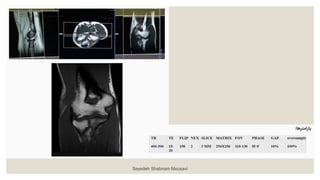

◦ ‫آگزیال‬ T1W ‫ضخامت‬ ‫با‬ ۳ ‫میلیمتری‬ : ◦ ‫به‬ ‫و‬‫بورونال‬ ‫صدحه‬ ‫رو‬ ‫را‬ ‫آگزدال‬ ‫مقاطع‬ ‫و‬ ‫داخلکی‬ ‫برککدل‬ ‫اپکی‬ ‫از‬ ‫بکه‬ ‫خطکی‬ ‫موازات‬ ‫بچیریک‬ ‫گذرد‬ ‫می‬ ‫خارجی‬ . ‫را‬ ‫مقکاطع‬ ‫موقعیکت‬ ‫بریک‬ ‫چک‬ ‫نیز‬ ‫ددد‬ ‫صدحه‬ ‫دو‬ ‫در‬ . ‫صکدحه‬ ‫در‬ ‫اساخوا‬ ‫به‬ ‫ومود‬ ‫مقاطع‬ ‫بریک‬ ‫چک‬ ‫ساجیاال‬ ‫باشرک‬ ‫بادک‬ ‫ساوک‬ ‫و‬ ‫بازو‬ . ‫هکا‬ ‫ش‬ ‫بک‬ ‫تعکاد‬ ‫تکا‬ ‫فوسا‬ ‫انو‬ ‫اوسن‬ ‫از‬ ‫باالت‬ ‫ش‬ ‫ب‬ ‫دو‬ ‫بادک‬ ‫راددکال‬ ‫وزداه‬ ‫توب‬ ‫از‬ ‫ت‬ ‫پادی‬ ‫مقطع‬ ‫دو‬ ‫دهک‬ ‫پوشش‬ ‫را‬ . ‫و‬ ‫باال‬ ‫در‬ ‫اشباع‬ ‫بانک‬ ‫گذاشا‬ ‫وق‬ ‫وک‬ ‫پاسسیشک‬ ‫آرتیدنکت‬ ‫از‬ ‫مقکاطع‬ ‫پادی‬ Seyedeh Shabnam Mousavi

• 12.